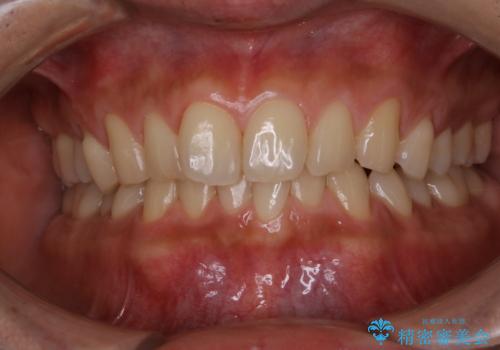

毎日コーヒーを飲む 歯を白くしたい

- 毎日コーヒーを飲むため、歯の着色がとっても気になるとのことでした。歯科でのクリーニングは2.3年ぶりのため全体的にきれいにしてほしいとのことでした。

PMTC60分コースを行いました。

またPMTCを行うことで、ご自身本来の歯の色になり自然な明るさになります。